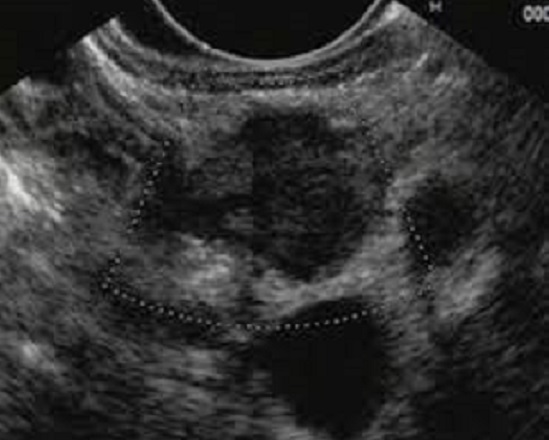

Image echographique d'un

tumeur endocrine pancreatique de petite taille .

Aspect echographique habituelle : hypoechogen ,

homogene et bien limite |

Image echographique du

tumeur endocrine de grand taille du pancreas .

Aspect echographique est hypoechogene , parfois

heterogen , multilobulaire et contour tres nette